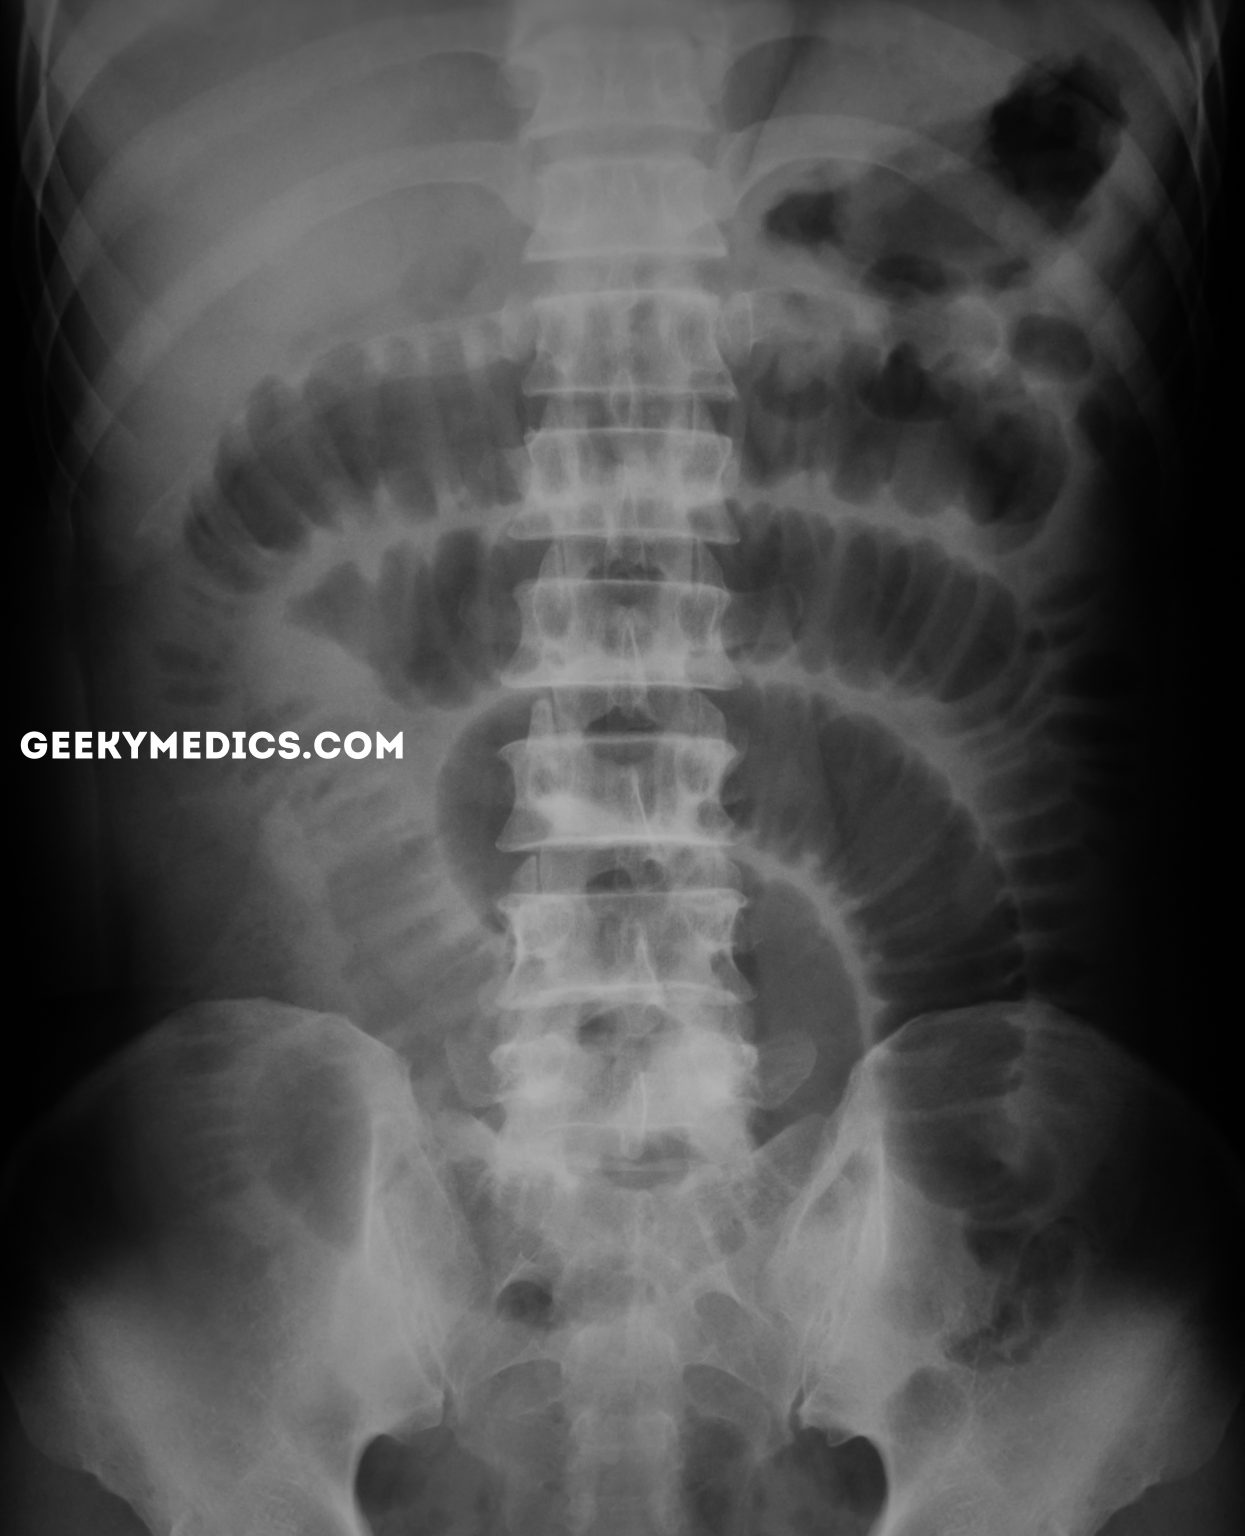

From geekymedics.com

Bowel Obstruction Small Bowel Large Bowel Geeky Medics Explain Short Bowel In short bowel syndrome, your stomach can make too much acid, called gastric hypersecretion. Short bowel syndrome is a problem you get if you've had surgery that removed a lot of your small intestine. It can happen because too much of the small intestine is missing or because it is not working as well as it should. In people with. Explain Short Bowel.

From calgaryguide.ucalgary.ca

Small Bowel Obstruction Findings on XRay Calgary Guide Explain Short Bowel It can happen because too much of the small intestine is missing or because it is not working as well as it should. Unchecked, this can lead to heartburn, ulcers and,. Cramping and bloating in your belly. If you don't have enough small intestine,. Treatments for short bowel syndrome include medication, changes to diet. Edema (swelling) in your legs. In. Explain Short Bowel.